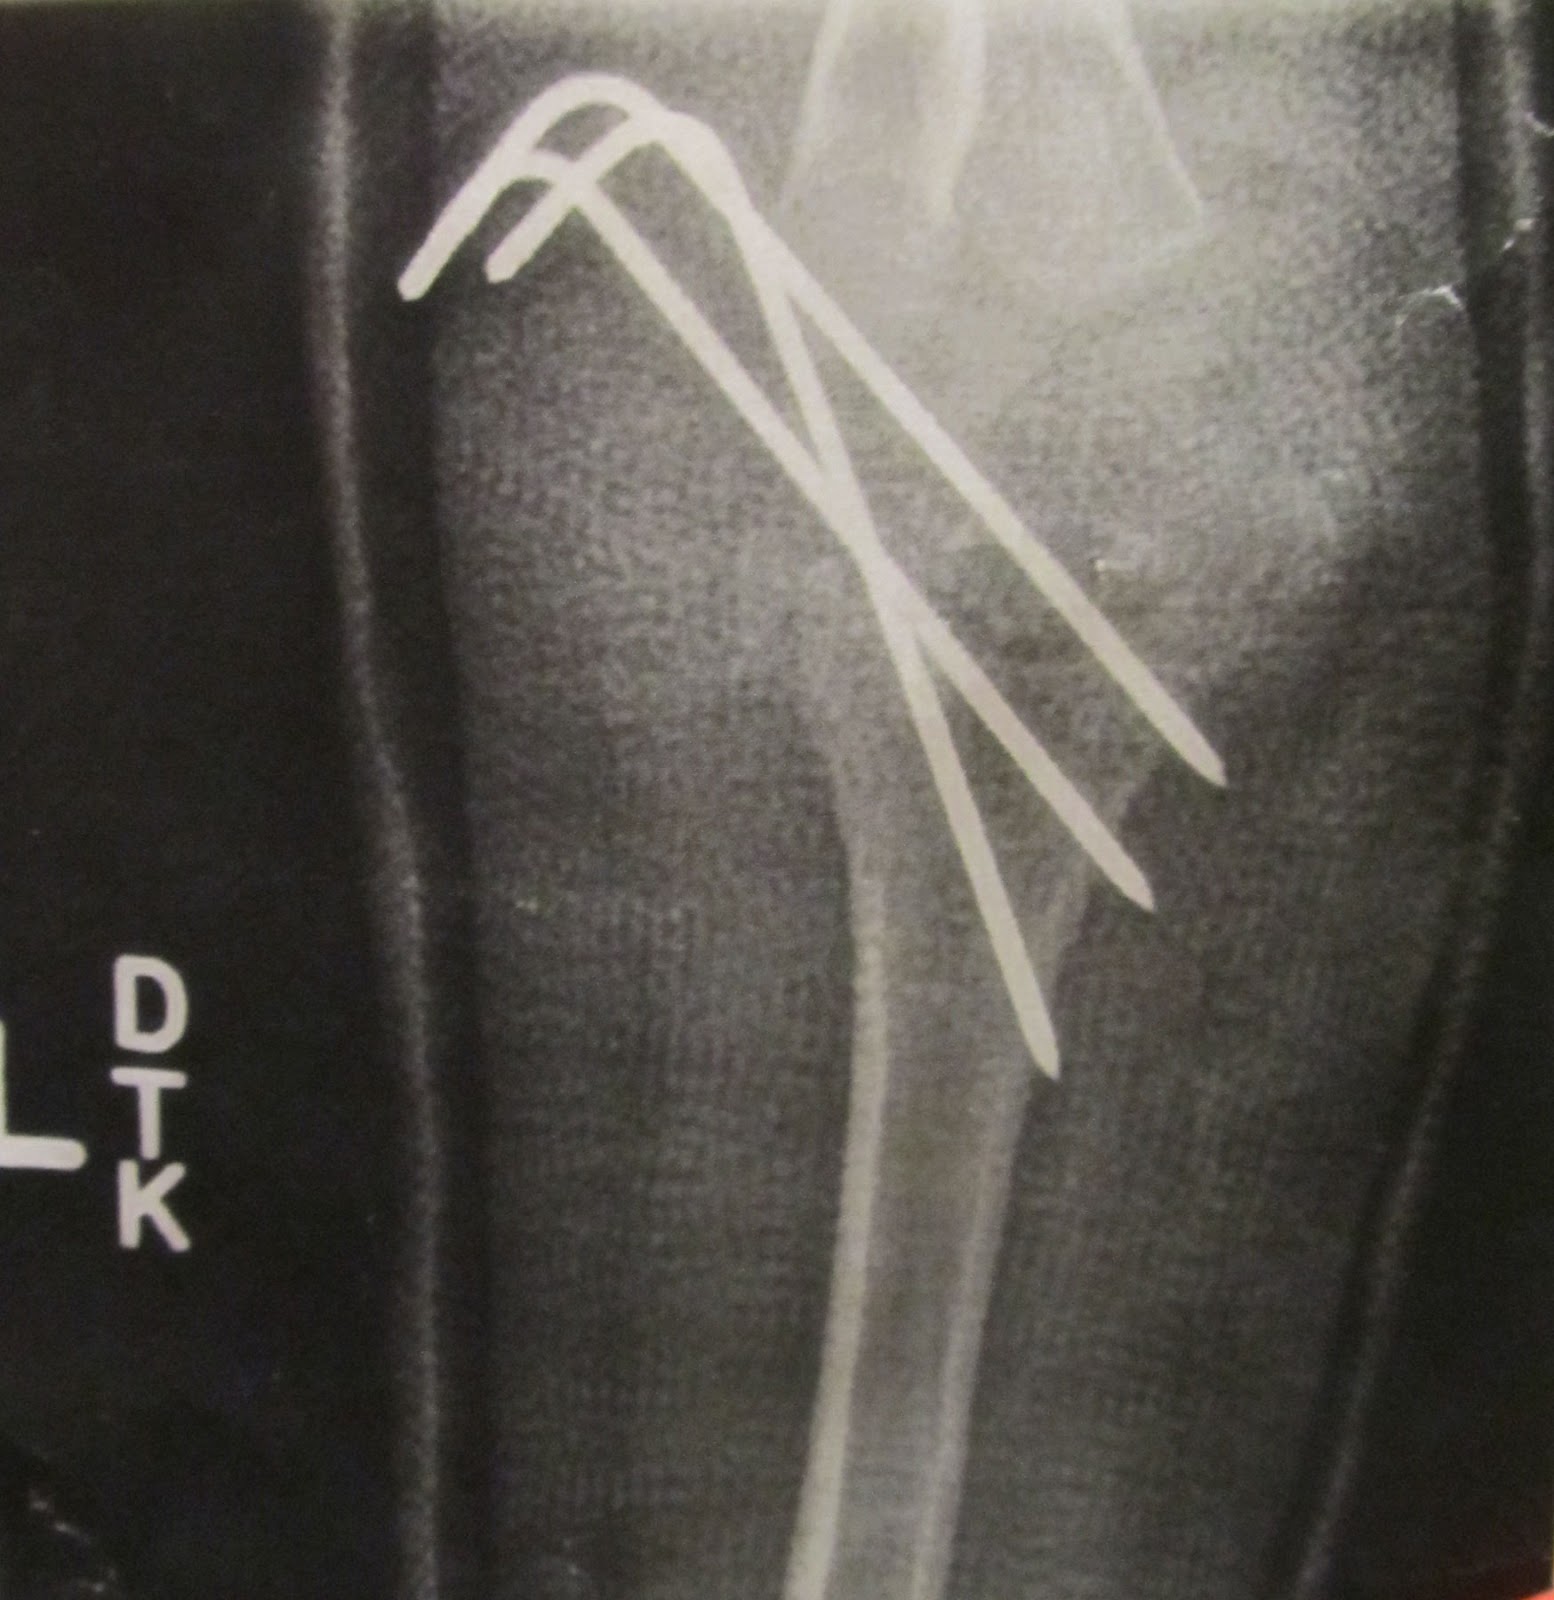

Broken Arm With Metal Pin, Xray Photograph by Science Source Fine A Broken Arm With Pin Patients often ask, “will the plate have to be taken out?” during our discussions about fixing bad wrist fractures or fractures in other parts of the hand and arm. If you think you (or someone you are with) have broken an upper arm, you should seek medical attention. A broken arm happens when any of the three bones in your. A Broken Arm With Pin.

AI Generative Xray image in a hospital of a broken arm with metal pins A Broken Arm With Pin Your healthcare provider may either perform a closed reduction (in which the skin is not cut) or an open reduction (in which an incision is made to reset the bone with pins, screws, and other appliances). The type of surgery you. Sometimes you can feel numbness or tingling in your arm. Some fractures can get straightened without surgery and held. A Broken Arm With Pin.